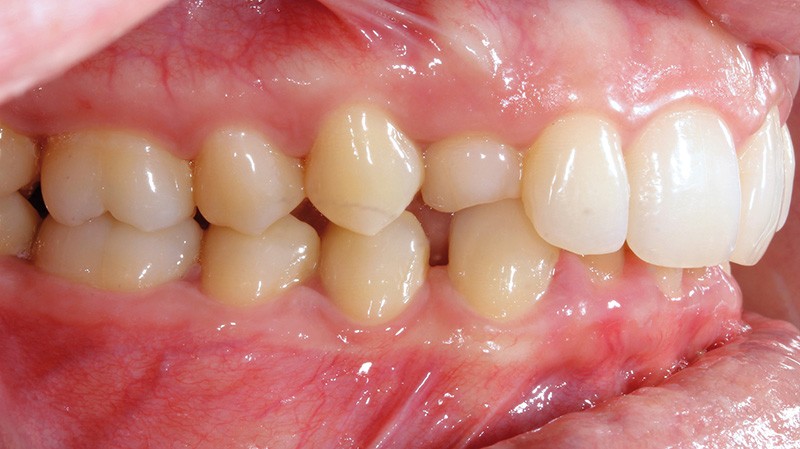

Aline se présente à la consultation pour une demande esthétique concernant ses deux canines lactéales qu’elle trouve trop petites et trop blanches (fig. 1a). Elle présente une classe II squelettique légère sur un schéma méso-divergent. D’un point de vue dentaire, une supraclusion est associée à une classe II d’Angle complète à gauche et de 4 mm à droite. Les canines maxillaires sont incluses (une vestibulaire et une palatine), avec persistance de leurs dents lactéales sur l’arcade (fig. 1b-h).

Un protocole orthodontico-chirurgical avec avancée mandibulaire est envisagé pour assurer un bon soutien labial, mais cette option est refusée par la patiente qui craint un visage trop carré. Concernant l’inclusion des canines maxillaires définitives, plusieurs thérapeutiques sont envisageables : 53, 63, 13, 23, ou 53, 63, 14, 24 peuvent être extraites, avec pour conséquence une classe II thérapeutique au niveau des molaires en fin de traitement. Cependant, la patiente souhaite mettre en place ses canines incluses pour conserver tout son capital dentaire et rétablir un idéal fonctionnel et esthétique au niveau des dents antérieures (fig. 2).